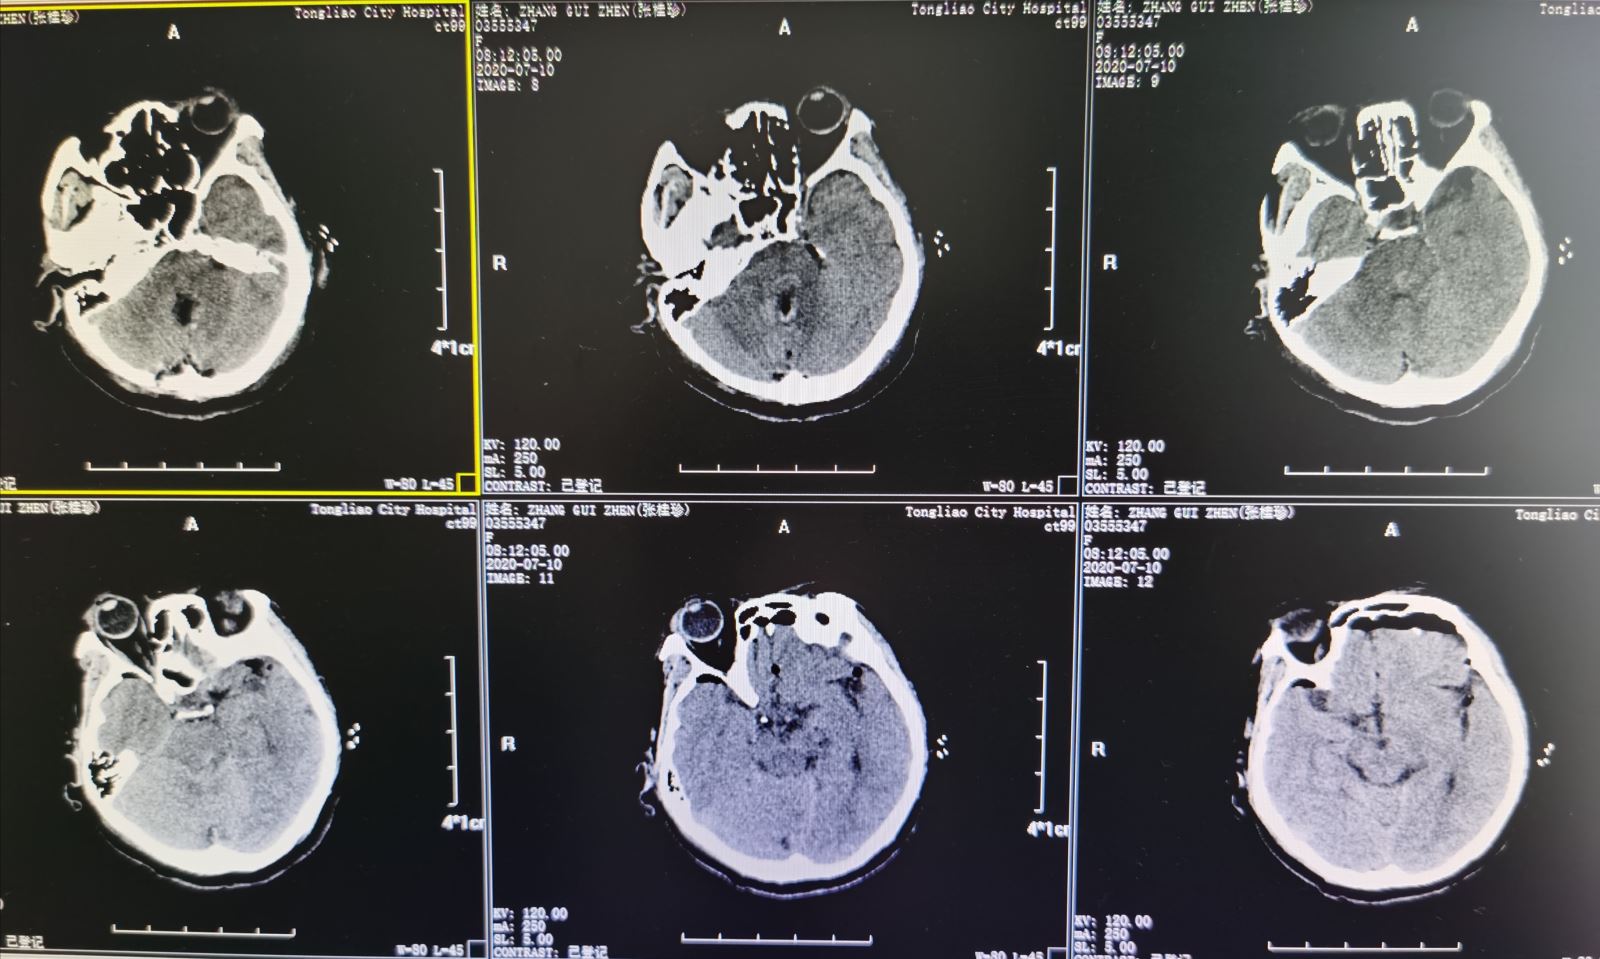

张某,女性,68岁,患者来我院就诊前3天出现无诱因间断性头晕、恶心、复视,偶有出现回答错误,走路不稳并向右侧偏等症状。在当地医院进行相关检查,头颅MRI(颅脑核磁共振)检查提示为脑桥囊性占位。为进一步诊治来我院就诊。查体:该患者左眼轻度外展,右侧肢体肌力4+级,精细动作差,病理反射阴性。头颅MRI增强扫描,结果提示为脑干肿瘤,收入我院东院区神经外科。